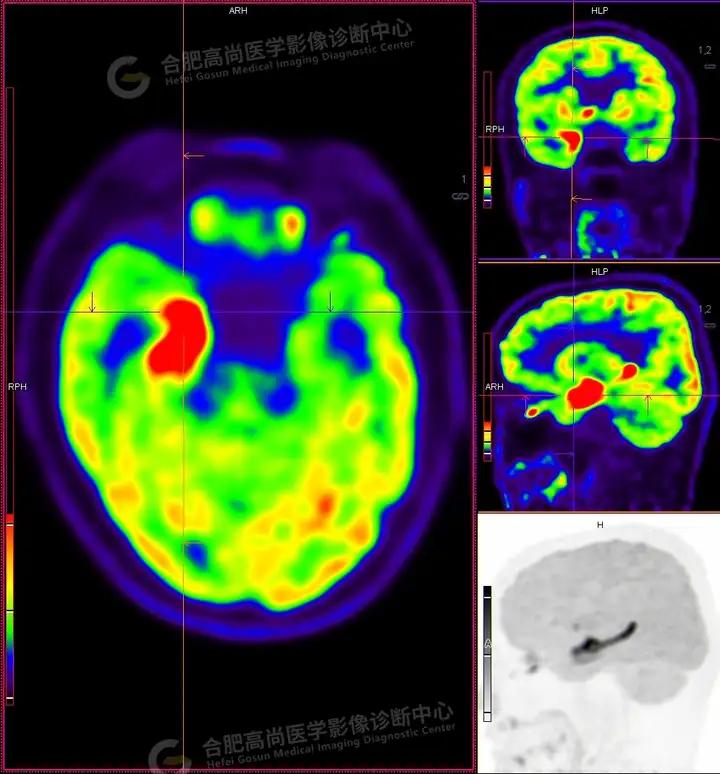

18F -FDG PET/CT检查图像:

18F -FDG PET/CT检查所见:

发作间期显像:PET显像双侧海马呈放射性摄取异常增高,以右侧明显,右侧海马SUVmax16.1、SUVavg4.4,左侧海马SUVmax7.3、SUVavg3.1(同层面额叶脑皮质SUVmax5.9、SUVavg2.3);CT示左侧海马体积较右侧似轻度缩小,左侧侧脑室颞角轻度增宽。PET显像右侧杏仁核及右侧基底节区局灶性放射性摄取异常增高,SUVmax14.1、SUVavg5.7(左侧SUVmax5.1、SUVavg3.6);CT示右侧杏仁核及右侧基底节区大小、形态正常,未见异常密度灶。

18F -FDG PET/CT检查结论:

发作间期显像:双侧海马、及右侧基底节区FDG代谢异常增高,考虑致癫灶可能大,请结合临床。